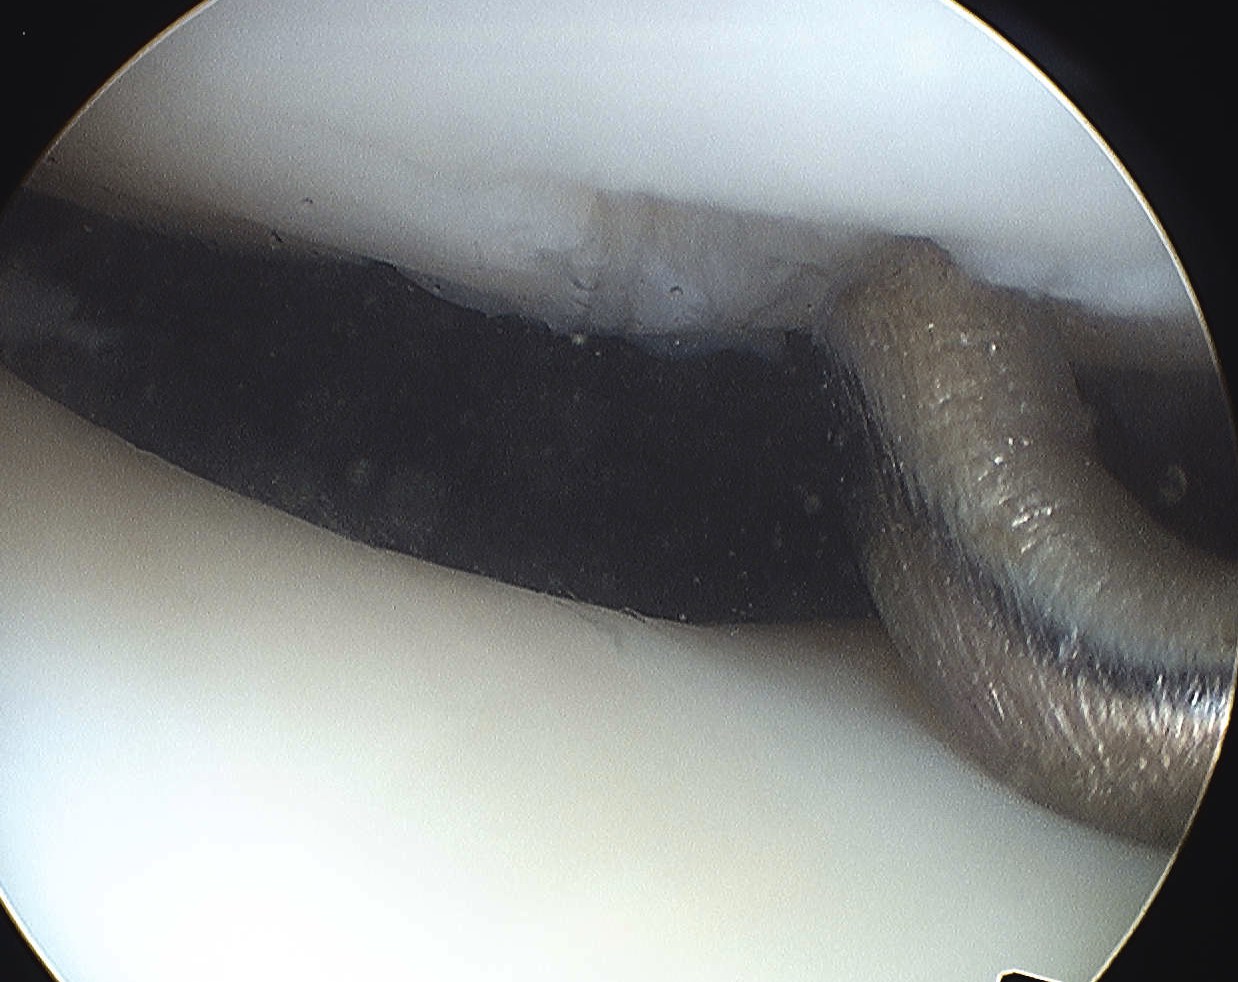

Arthroscopy

Assess Patella and Femoral Lesions

1. Small pieces cartilage

- remove loose bodies

- microfracture if necessary

2. Large Osteochondral Fragment

- usually medial patella or lateral femur

- open approach to knee

- reduce and fix with bioabsorbable compression screws / pins